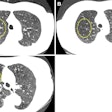

Low-dose CT ties emphysema to mortality in previous smokers